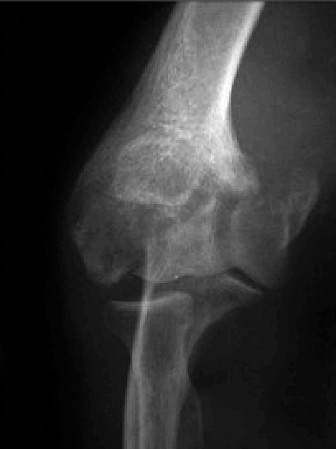

It should be noted that reverse total shoulder arthroplasty is also the procedure of choice in patients with cuff-tear arthropathy (aka rotator cuff arthropathy). Characteristics of cuff-tear arthropathy include superior migration of the humerus due to a massive rotator cuff tear, glenohumeral joint destruction, subchondral osteoporosis, and humeral head collapse (see Fig. 2–17). A reverse total shoulder

Figure 2–17_X-rays of a patient showing evidence of cuff tear arthropathy. The humerus is migrated superiorly, the glenohumeral joint is destroyed, there is subchondral osteoporosis, and the humeral head is collapsed. (From Ecklund KJ, Lee TQ, Tibone J, Gupta R. Rotator cuff tear arthropathy. _J Am Acad Orthop Surg. 2007;15(6):340–349.)